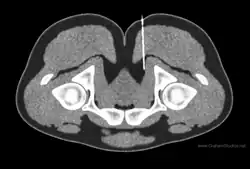

Ultrasound guided femoral nerve block

Ultrasound-guided peripheral nerve block is a procedure that allows real-time imaging of the positions of the targeted nerve, needle, and surrounding vasculature and other anatomical structures.[16] This visual aid increases the success rate of the block and may reduce the risk of complications.[17][18] It may also reduce the amount of local anesthetic required,[19] while reducing the onset time of blocks.[20] Ultrasound has also resulted in an exponential rise in fascial plane blocks.[21] Ultrasound is particularly well-suited for regional anesthesia, since many of the anesthesia targets (e.g., brachial plexus, femoral nerve) have large blood vessels that travel with the target nerves.[10] Direct visualization of nerves is not just important for localization, but also to ensure that the injected material surrounds the nerve. Likewise, visualization of blood vessels is important to ensure that needle placement avoids blood vessels, which often travel directly parallel to nerves.[20]